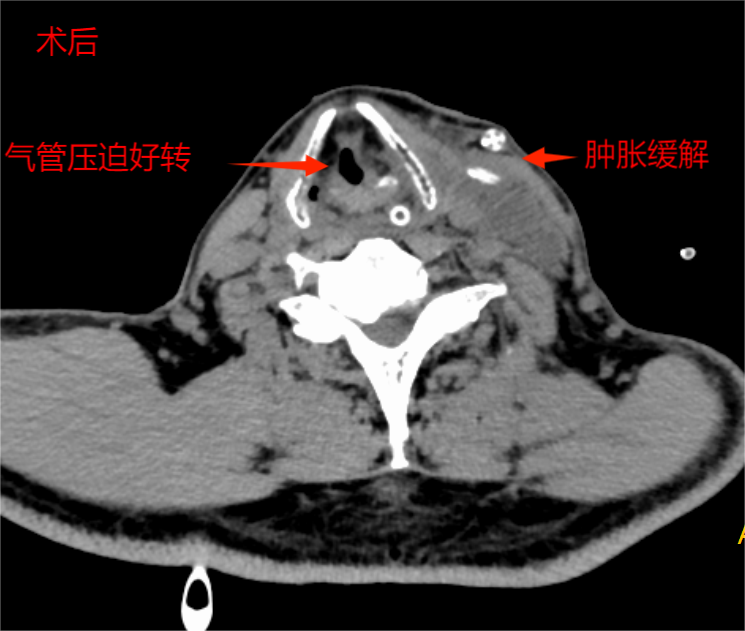

经过多科精心治疗与严密监测,患者感染得到控制,呼吸功能显著改善,复查CT颈部肿胀较前消退,气道压迫表现较前明显缓解,达到安全拔除气管插管的标准。当李伯成功脱离呼吸机,恢复自主呼吸的那一刻,标志着治疗取得了阶段性重大胜利。拔管第二天,李伯在呼吸与危重症医学科主管医师周世全和康复科治疗师莫兆财专业指导下便可在床旁活动。这不仅同步指导患者进行基础呼吸功能训练,还可以加速呼吸功能恢复,循环地进行了体能训练。

术前术后对比